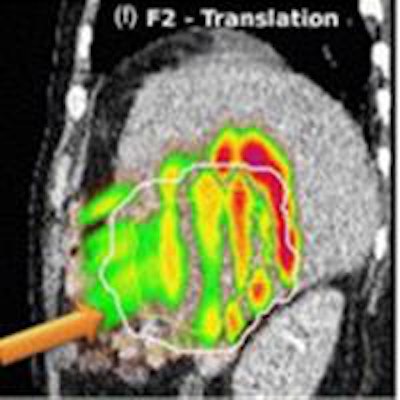

Left: PCA motion prediction using 2D fiducial markers. Right: PCA prediction using either tracked diaphragm SI-motion or 2D markers motion as predictor.

Left: PCA motion prediction using 2D fiducial markers. Right: PCA prediction using either tracked diaphragm SI-motion or 2D markers motion as predictor.The researchers examined the accuracy of their motion reconstruction by comparing the predicted results with the ground-truth motion (extracted directly from the 4D MRI data). Averaged over all 11 subjects, for 99% of predicted positions, median (maximum) errors were better than 2.63 (5.67) mm when tracking fiducial markers. Results were similar for tracking diaphragm motion, which resulted in a median (maximum) 99% prediction error of 2.7 (4.2) mm.

Comparing absolute dose differences between ground truth-based and prediction-based plans (using fiducial markers) showed that motion predictions from the translation-only scenario were poor, with maximum dose differences of more than 50%. Plans based on PCA-predicted motion, on the other hand, were similar to those based on ground-truth motion. Here, absolute dose differences of more than 5% occurred in only 3.61% (median) or 15.13% (maximum) of dose calculation points in the irradiated volume. Similar results were seen when tracking diaphragm motion.